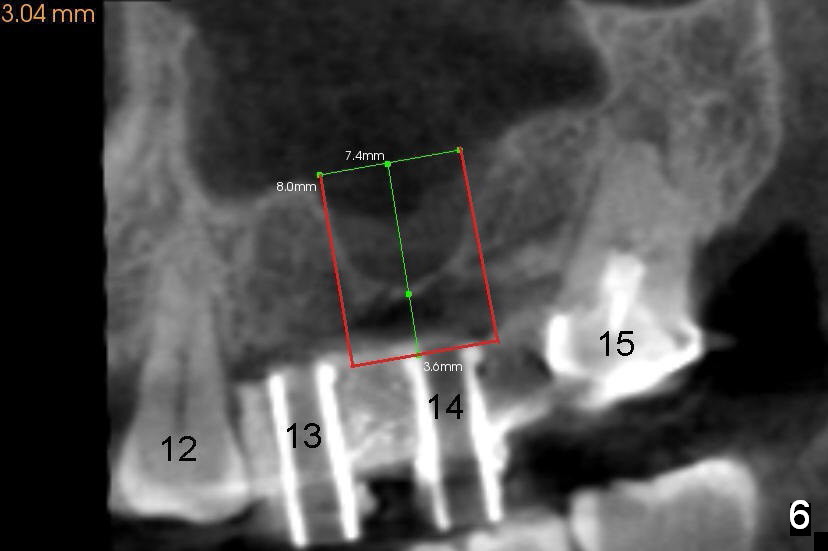

A man in his 70s had a partial denture in the upper left quadrant (Fig.1) prior to loss of #15, which was replaced by an implant (Fig.2). Lateral window sinus graft was tried without success in preparation for $14 implant placeement. Recently the partial was lost. Two missing teeth are going to be restored by implants with sinus lift in the crestal approach. Although the bone height is limited (2 mm), the implant at the site of #14 is able to obtain primary stability by engaging into the sides of the sinus floor (Fig.2 arrowheads).

After crestal incision, a 3.5 or 4 mm trephine bur is used for 2 mm at #14. The regional sinus floor is lifted using a Bicon flat-end osteotome, followed by bone graft and taps. If the 6x11 mm tapered tap does not gain stability (Fig.3), use either 6x11 mm round tap (Fig.4) or 7 or 8x11 mm tapered tap (Fig.5). If the last does not work, try a larger round tap (Fig.6). In all, the sinus floor is pushed upstairs and an implant is inserted to be engaged into the sides of the sinus floor (Fig.7).